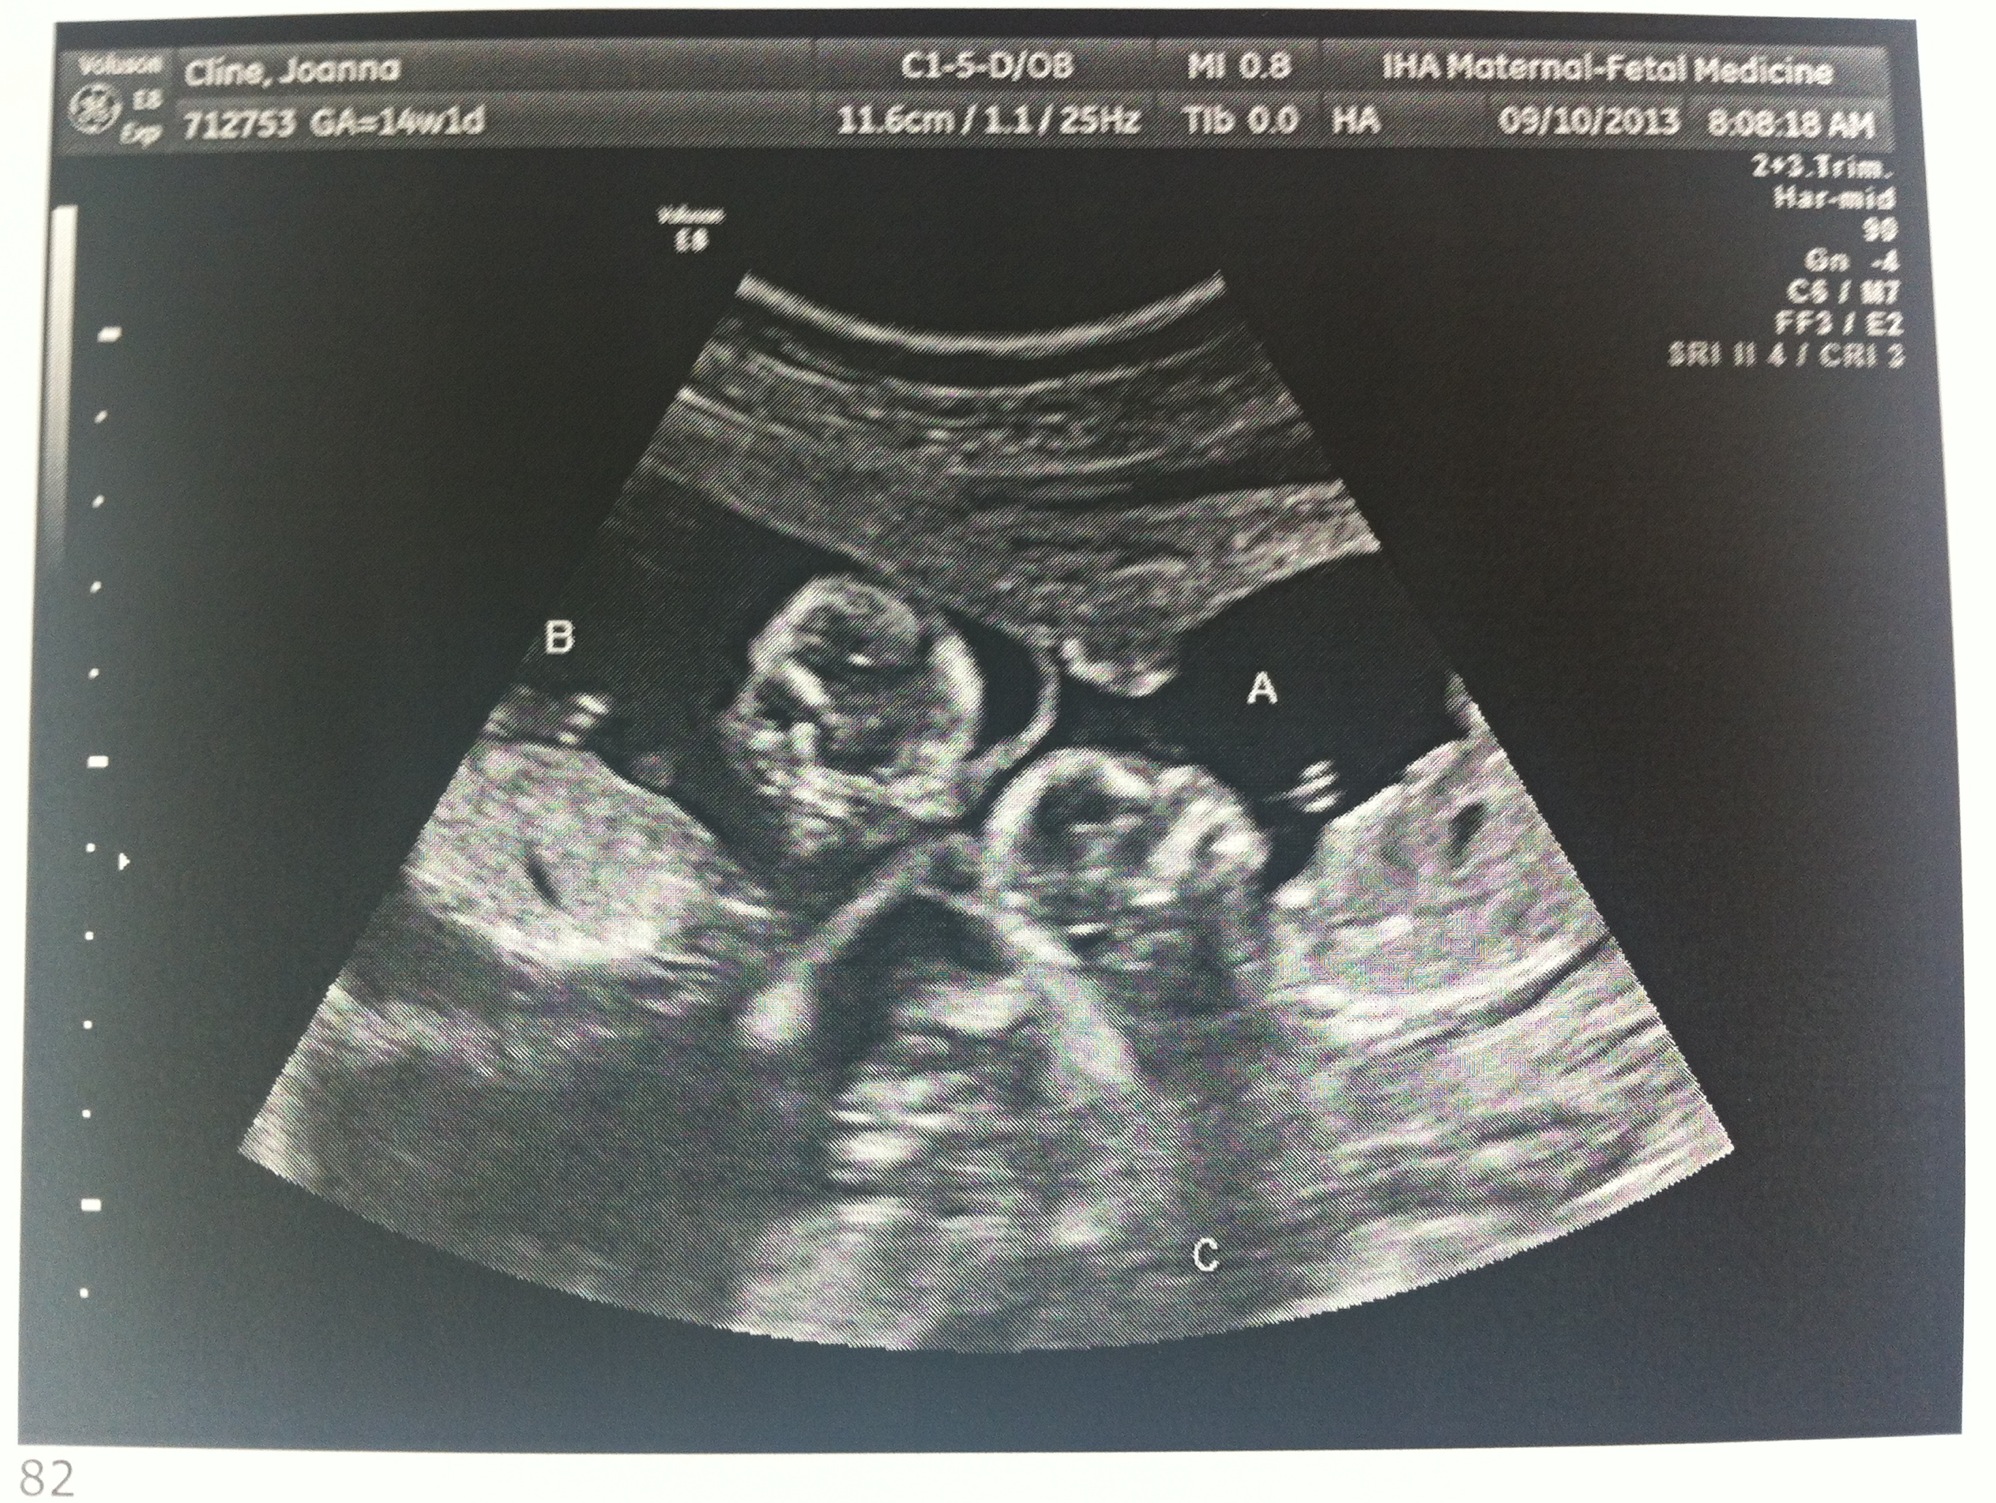

Baby A – is a BOY!

Baby B – is a GIRL!

Baby C – is a BOY!

A is 170 grams, B is 175 grams and C is 178 grams so they’re all measuring well. Grow, grow, grow!